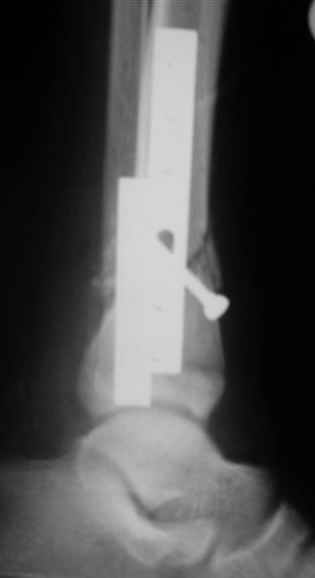

Re: дистальный тиб.фиб. перелом

Помятуя наш недавний разговор о фиксации м.б. кост, высылаю послеоперационные картинки..

Напомню- разбирали случай 17 летнего молодого человека перелом дист тиб.фиб. хирургия после 3 недель с момента травмы( безуспешные попытки закрытой репозиции) Раны заживают первичным натяжением, занимается физиотерапией, пока никаких проблем не наблюдается